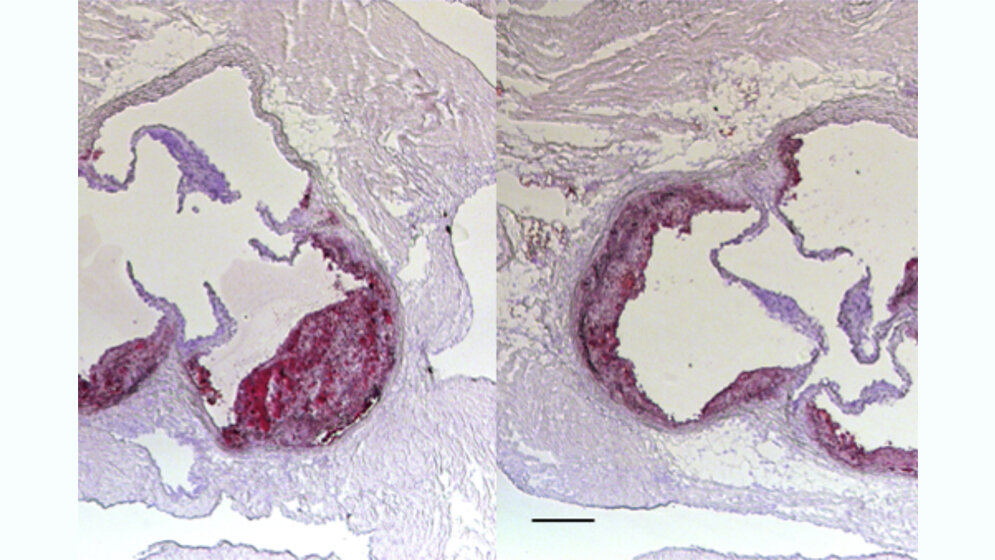

Interferon-gamma ist ein immunstimulierendes Protein. In den genetisch veränderten Mäusen mit CD40L-Mangel fanden die Wissenschaftler kleinere, stabilere atherosklerotischen Plaques. Die Hemmung von CD40L könnte demnach Ablagerungen in Blutgefäßen stabiler machen und damit Herzinfarkte verhindern. Ähnliche Befunde zum Schutz durch CD40L-Mangel traten bei Mäusen mit CD40-Mangel in dendritischen Zellen auf. In Blutplättchen beeinflusste ein Mangel an CD40L die Atherosklerose nicht. Jedoch traten weniger Atherosklerose-bedingte Blutgerinnsel auf.